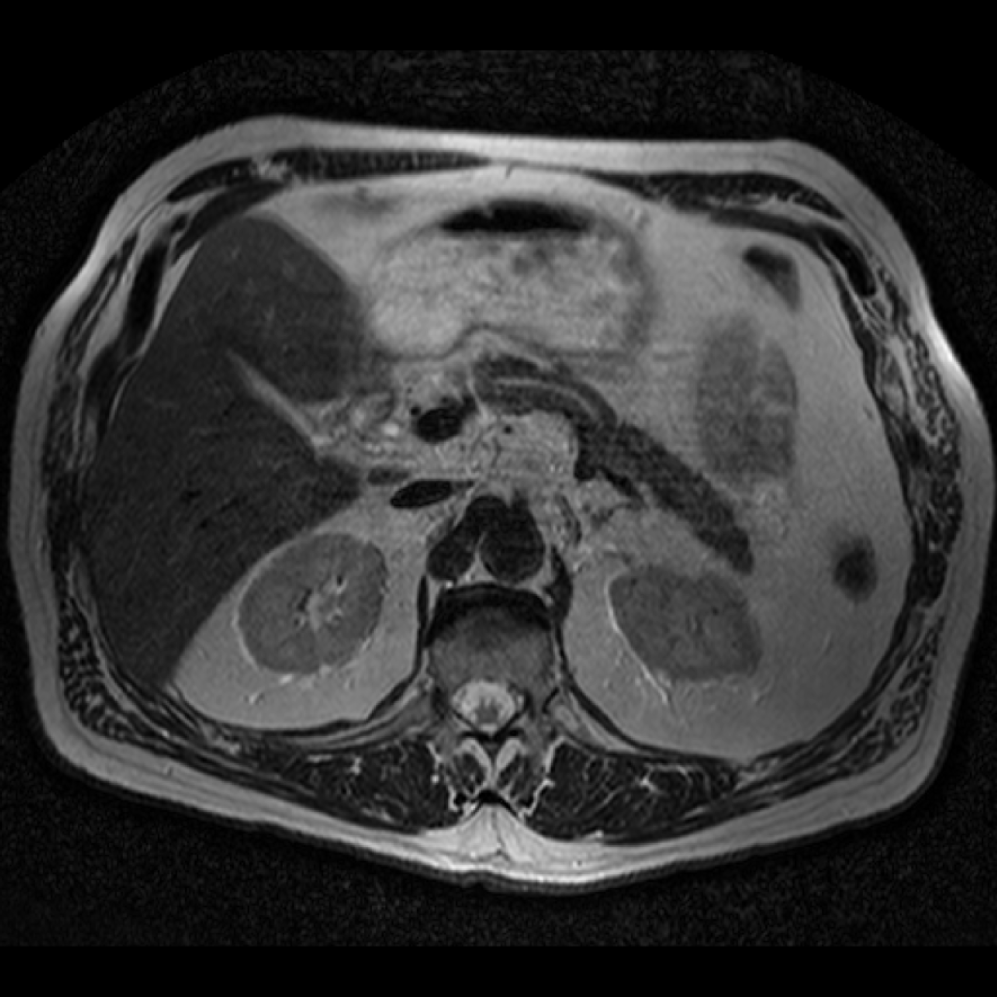

Accurate pancreas segmentation is a critical prerequisite for precise cyst analysis and classification. Recently, we developed PanSegNet [zhang2025large], a novel segmentation architecture incorporating linear self-attention layers [zhang2022dynamic] within the nnUNet framework [isensee2021nnu] to enhance global information modeling capabilities while maintaining computational efficiency (Fig. 1). PanSegNet demonstrated exceptional segmentation performance across both T1W and T2W modalities, achieving mean dice scores of 86.817.30% and 89.626.38%, respectively (Table 1, Fig. 2b-c). This performance significantly exceeded that of Swin-UNETR [hatamizadeh2021swin], one of the most used state-of-the-art transformer-based medical segmentation models, which achieved dice scores of 79.091.40% and 76.290.66% for T1W and T2W, respectively (). In this study, we integrated PanSegNet into our Cyst-X engine along with a classifier for risk prediction. In Section 2.2, we show that the choice of segmentation model affects the classification results. The performance advantage of PanSegNet was consistent across all seven medical centers, demonstrating robust generalization despite variations in imaging protocols and equipment (Table 1). This cross-institutional reliability is particularly important for clinical applications, where model performance must remain consistent regardless of imaging site or acquisition parameters.

Each patient was categorized into one of these three ground truth classes: no risk/control, IPMN low-risk, or IPMN high-risk. To evaluate variability in image acquisition, we applied uniform manifold approximation and projection (UMAP) to image quality indicators, revealing distinct clustering patterns by imaging center and slice thickness. This heterogeneity reflects real-world clinical variability, enhancing the dataset’s generalizability while presenting technical challenges for model development. Fig. 6 shows examples of low-grade, high-grade, and cancer developing IPMNs from the Cyst-X dataset.

4.2 Image preprocessing and segmentation